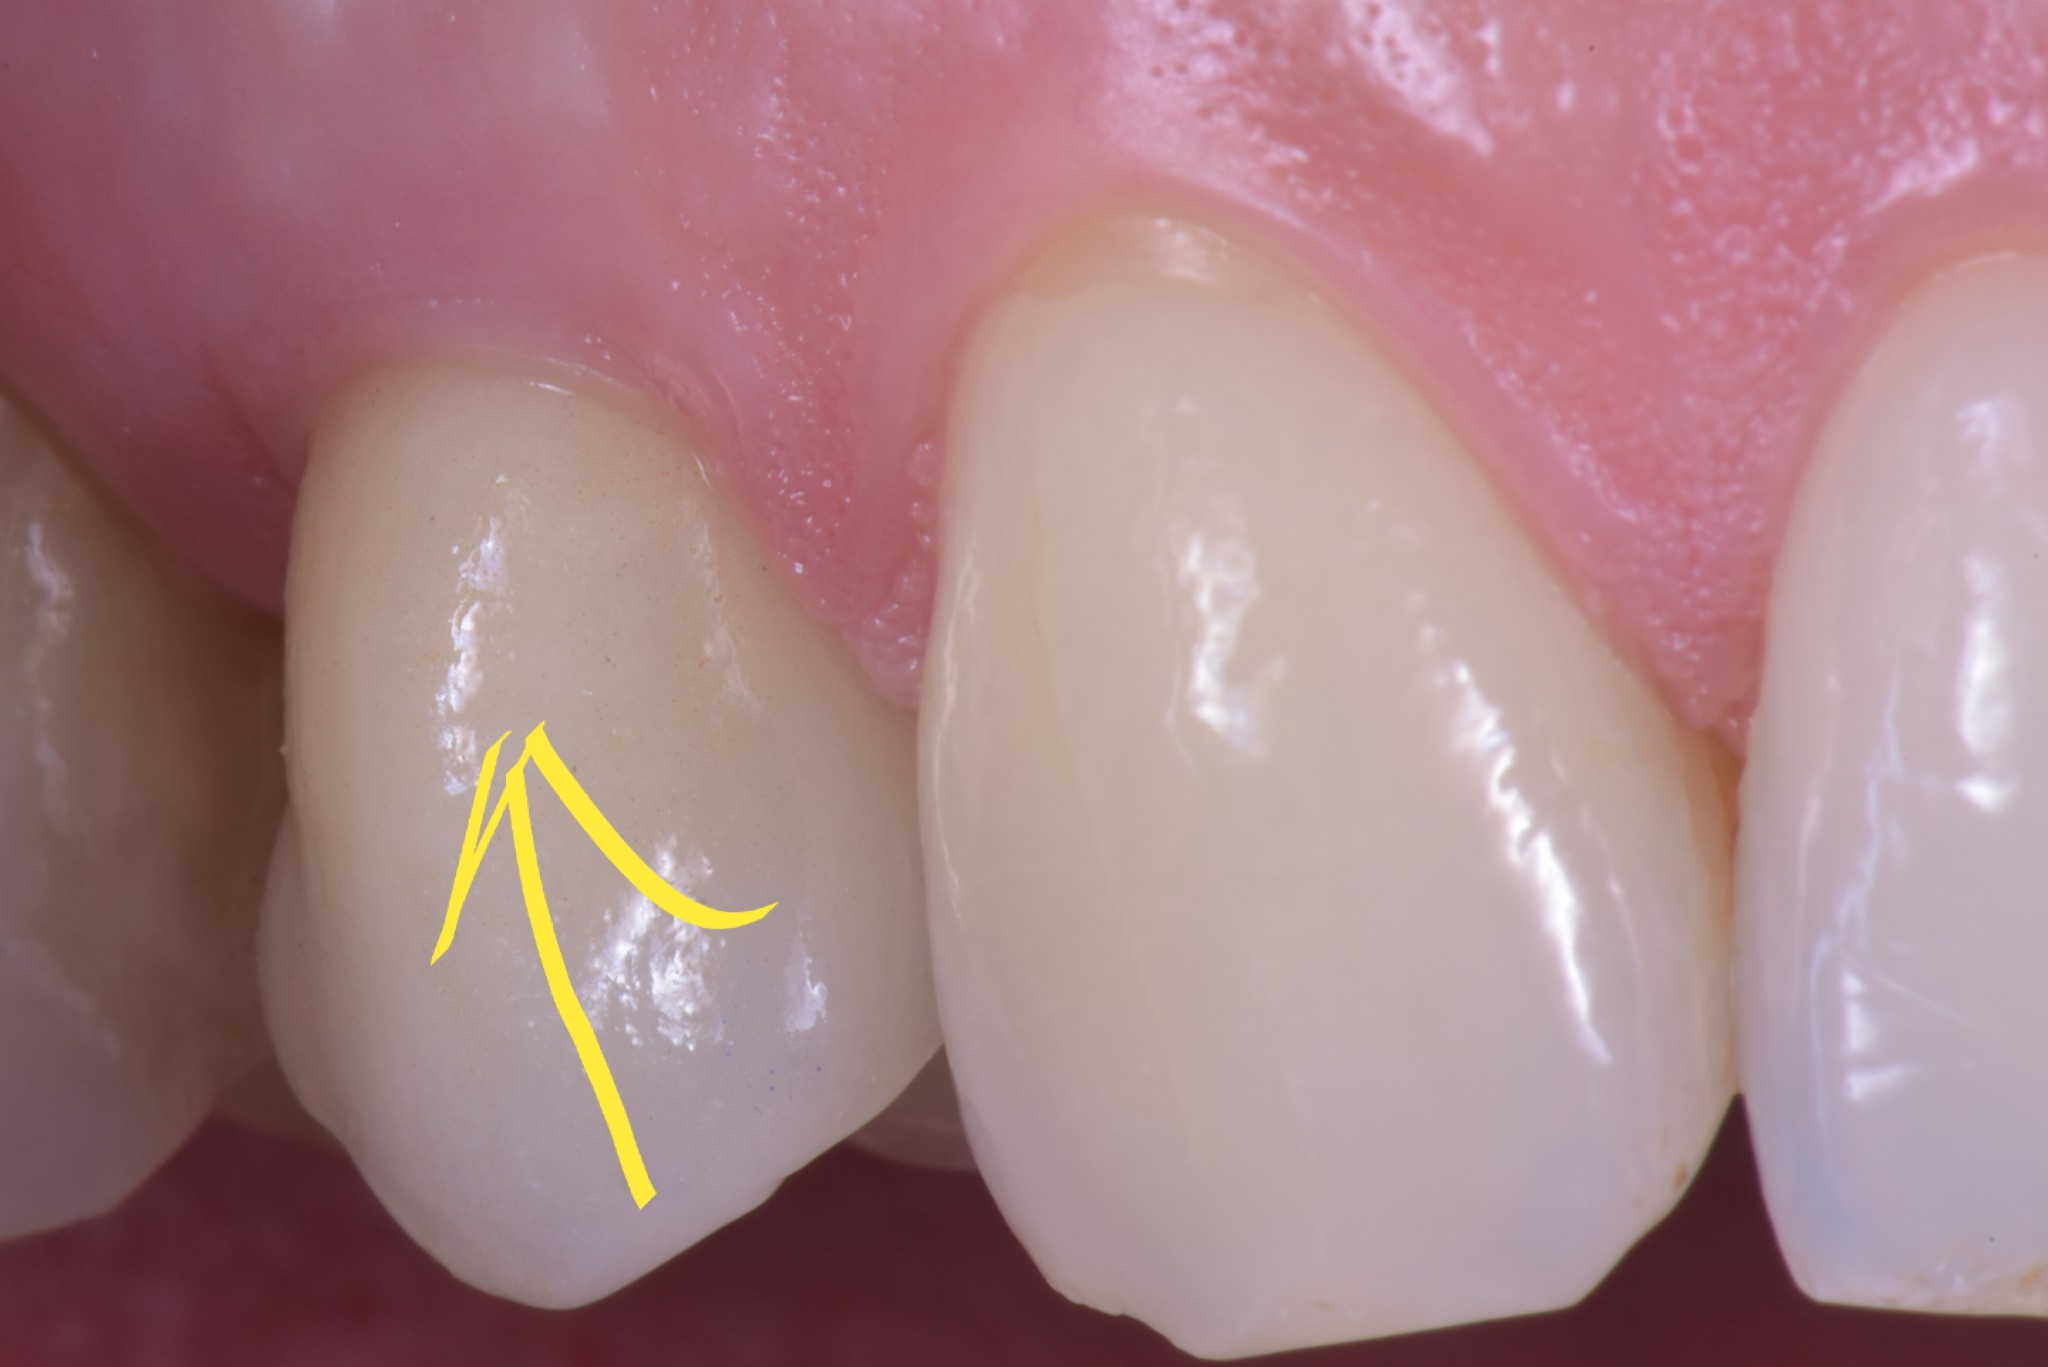

Un dente su impianto oggi ha la possibilità di avere questo aspetto

O questo, se vuoi un esempio frontale.

Soprattutto se si parte da una condizione tissutale ottimale.